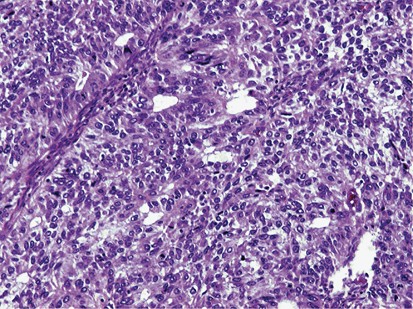

Low-Grade ECa and Undifferentiated Carcinoma (Dedifferentiated Carcinoma)

This uncommon high-grade carcinoma can arise in the endometrium or ovary and is characterized by the combination of a low-grade endometrioid (FIGO grade I or II) juxtaposed to an undifferentiated carcinoma (Figure 11, left and right).37, 38, 39 The undifferentiated component can be seen in the primary tumor or exclusively in the metastases (which can be at unusual sites).37 It is characterized by variably sized monotonous often non-cohesive cells with high nuclear-to-cytoplasmic ratio, dispersed chromatin, and small nucleoli with brisk mitotic activity. The cells are often arranged in sheets (Figure 12) but myxoid background, abrupt squamous differentiation, trabecular growth, and spindle or rhabdoid cells may be seen (Figure 13a–d). Prominent necrosis and conspicuous vascular/lymphatic space invasion are common. The undifferentiated component is variably positive for keratin cocktail, EMA, Cam 5.2, and keratin 18. Initially, it was found that the expression of the first three markers had a tendency to be focal and in some cases more than 1 block had to be tested.38, 39 However, it has recently been found that 54% of undifferentiated carcinomas are positive for keratin cocktail with either a patchy or diffuse staining pattern40 and 60% are positive for keratins 8/18.40 Cyclin D1 can be multifocally or diffusely strongly positive,41 p53 is typically diffusely positive, and diffuse p16 is seen in up to 50% of tumors. Chromogranin and/or synaptophysin can be focally positive (≤10% of cells) but this finding does not warrant designation as a neuroendocrine carcinoma.42 ER/PR expression is usually low or absent. Up to 80% of the tumors are PAX-8 negative.40 In addition, INI-1 shows retained nuclear expression, although experience is limited.39 Undifferentiated carcinoma is often associated with loss of mismatch repair proteins (more frequently loss of MLH1/PMS2 and sometimes loss of MSH6).39, 40, 43